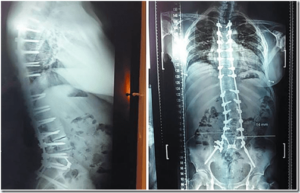

¿Puedes AJUSTARTE si te han operado de la columna o si te han implantado fijaciones con tornillos, por ejemplo?

Muchas veces las personas que nos visitan están intervenidas quirúrgicamente en la columna. En ocasiones tienen placas, tornillos, prótesis de cadera o de rodilla, etc.

Todas estas personas se pueden ajustar teniendo todo esto en cuenta; lo que varía, y esto dependerá de cada quiropráctico, será la manera o técnica elegida para realizar el ajuste quiropráctico.